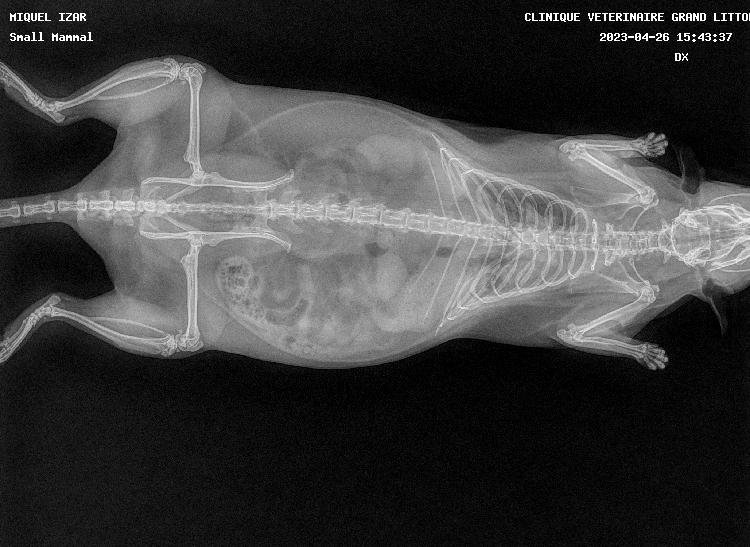

pas de super bonnes nouvelles car les deux miss ont les poumons atteints, si je m'en doutais un peu pour Izar qui ronflait depuis mars (c'est vite parti avec le collyre dans le nez) et respirait une peu trop vite, je suis tombée des nues pour Thari, qui me fait un coup à la Seren : zéro symptôme mais poumons pourris (si seulement elle pouvait avoir la même longévité :siffle:). Les deux pupuces sont donc sous deux antibiotiques (un par injection et un par voie orale) et Izar à en plus un AINS. Contrôle radio prévu dans quelques semaines.

Petites photos des belles et radios en spoil

Thari

Thariprofildroitavril2023.jpg.5c18040e016999d23a3866f24f5c81e8.jpg

Tharifaceavril2023.jpg.6759497e1a95d196154db5a6af44e844.jpg

Thariprofilgaucheavril2023.jpg.297630575b4261f43627592bdb11e17a.jpg

Petites nouvelles des frangines. On est allé voir le véto d'Aix aujourd'hui et en regardant les radios, il ne trouve pas que celles de Thari soient mauvaises finalement. Pour Izar il trouve que ça ressemble à un épanchement, plutôt qu'une infection, il lui a donc fait une échographie et d'après lui, c'est effectivement de l'eau qu'elle a dans les poumons (origine inconnue).

Donc on arrête tous les traitements sur Thari et sur Izar, on garde juste l'antibiotique par injection et on rajoute un diurétique.